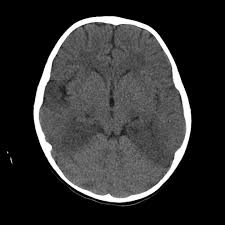

Mri is the imaging of choice in suspected cases of viral encephalitis, although ct scanning may be used where mri facilities are not available. A case of granulomatous hsv encephalitis: Hsv pcr and other infectious studies from the serum and csf were negative. Brain mri is shown in fig. Severe infection, particularly untreated herpes simplex virus (hsv) encephalitis, can cause brain hemorrhagic necrosis.

In children older than 3 months and in adults brain biopsy: Herpesviral encephalitis, or herpes simplex encephalitis (hse), is encephalitis due to herpes simplex virus. • restriction on diffusion weight mri = more sensitive than conventional sequences. Misra uk, hashmi aa, kalita j. Diagnostic uncertainty and empirical management in pcr negative encephalitis. It is a severe condition brain mri may show limbic encephalitis (55) or diffuse t2 and dwi hyperintensities in the white matter, associated with restricted diffusion (54). Herpes simplex encephalitis occurs as 2 distinct entities: Mri is the imaging of choice in suspected cases of viral encephalitis, although ct scanning may be used where mri facilities are not available. The patient had initially improved after medical treatment. Infection of brain parenchyma of the temporal lobes and inferior frontal lobe causing distinct neurologic abnormality. Dhawan a, kecskes z, jyoti r, kent al. Associated with hsv encephalitis (strong evidence). In addition, because of the involvement of the.

• occurs despite blood brain barrier with tight junctions. Encephalitis in the immunocompromised host. Mri is the imaging of choice in suspected cases of viral encephalitis, although ct scanning may be used where mri facilities are not available. It is a severe condition brain mri may show limbic encephalitis (55) or diffuse t2 and dwi hyperintensities in the white matter, associated with restricted diffusion (54). Diagnostic uncertainty and empirical management in pcr negative encephalitis.